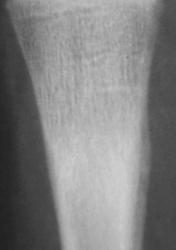

А с этим (помечено стрелками), что будем делать?

ИзображениеИзображение

Коллеги! меня тоже смущает участок, выделенный Валентином Львовичем стрелочками. Имеются округлой формы, мелкие участки перестройки костной ткани литического типа. Кортикальный слой муфтообразно утолщен с периоссальной реакцией. А нет ли там объемного образования?

Меня тоже смущает, и очень. Отправляйте к детским онкологам, пусть они контролируют. Основание: диафиз лучевой кости бульбообразно расширен ("поддут"), структура кости уплотнена муфтообразно/"пояском", менее выраженные, чем по переднему стенке кости, но аналогичные изменения отмечаются и по задней стенке диафиза, плюс периостальная реакция в прямой проекции.